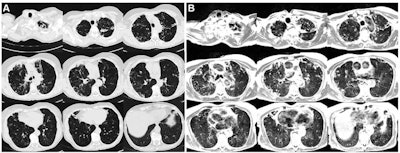

Campbell-Washburn's team conducted their study between November 2018 and December 2019 and included 24 participants with lung abnormalities; they compared breath-triggered T2-weighted turbo spin-echo MRI at 0.55 tesla with CT scans. The researchers assessed abnormal findings identified with MRI and CT using the kappa coefficient.

The researchers were able to obtain effective lung MR images with an average acquisition time of 11 minutes, and MRI detected a range of lung conditions comparably to CT (measured by kappa coefficient).